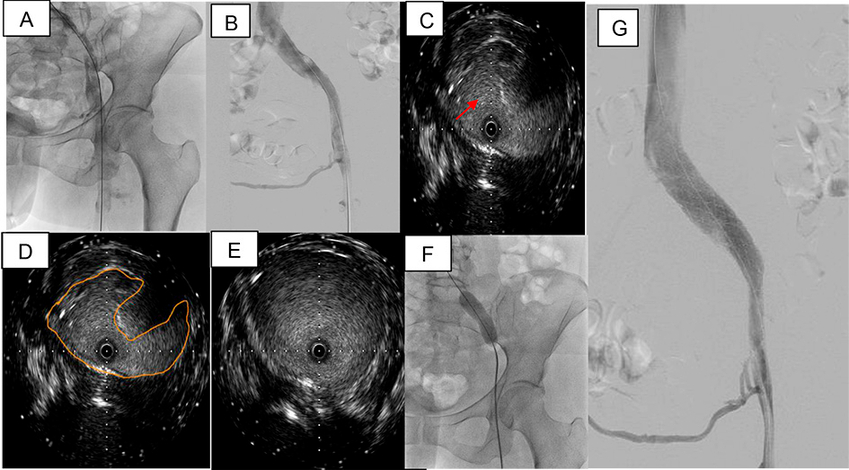

Se posiciona de prono a la paciente luego de anestesia general. Se emplea acceso poplíteo guiado por eco Doppler con introductor 5 French. La flebografía de miembro inferior izquierdo confirma oclusión vascular desde la vena femoral superficial en el segmento proximal, hasta la vena cava inferior, con circulación colateral de gran desarrollo y defecto de relleno endoluminal compatible con trombo reciente (Figura 1D). Con cuerda 0.035¨ Roadrunner® sobre catéter vertebral 4 French se logra recanalizar la oclusión del eje ilíaco y avanzar la cuerda cc) mediante sistema Power Pulse™. Luego de la espera de los correspondientes 30 minutos del tratamiento con trombolítico, se realiza angiografía, en que se observa repermeabilización del eje venoso izquierdo hasta la vena cava, con persistencia del defecto de relleno endoluminal (Figura 2A). Se continúa con tromboaspiración isovolumétrica activa con sistema AngioJet™ durante 130 segundos, tras lo cual se objetiva ostensible mejoría del flujo vascular y disminución significativa de la carga trombótica, sin evidencia de improntas o defecto de relleno en el ostium de la vena ilíaca izquierda (Figura 2B), hallazgo que no se corresponde a la habitual anatomía del síndrome de May-Thurner (SMT), en que hay compresión extrínseca del sistema venoso ilio-cava por el sistema arterial. Se continúa con evaluación por ultrasonido endovascular (IVUS), que evidencia disminución del calibre de la luz en la vena ilíaca primitiva proximal (en sentido del flujo) en la zona topográfica de la arteria hipogástrica, y ausencia de alteraciones en el ostium de la vena ilíaca primitiva izquierda (Figura 2 C-E). Se elige con estos hallazgos predilatación con balón 15 × 40 mm (Figura 2F) e implante de stent autoexpandible Abre™ de 20 × 100 mm (Figura 2G).

Este es un caso de trombosis venosa secundaria a compresión venosa dentro de la pelvis en un punto atípico, que no se corresponde con SMT. La compresión de la vena ilíaca izquierda por la arteria ilíaca interna ha sido descripta en otros reportes de casos como una variante del SMT 5,6. Las imágenes tomográficas no habían destacado un área de compresión clara. El uso de IVUS intraprocedimiento permitió ubicar la zona de la estenosis y guiar su tratamiento.